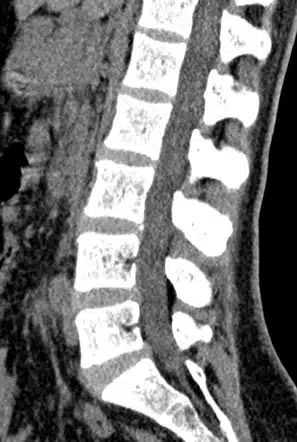

- CT scan – also known as Computed Tomography, this machine uses a series of x-rays along with computer processing to create detailed cross-sectional images. CT scans produce higher quality images that can also see organs and blood vessels. However, they are associated with more radiation exposure.